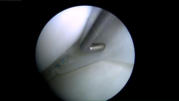

Arthroskopie =

Gelenkspiegelung

Arthroskopie = Gelenkspiegelung